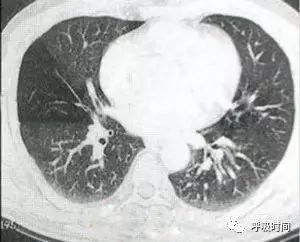

图 11 肺纤维化病变影——弥漫性特发性肺间质纤维化。双肺胸膜下可见网状影及条索影(蓝箭头)